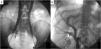

Cavografía a través de acceso femoral bilateral muestra vena cava inferior (VCI) completamente duplicada (A) con continuación ácigos bilateral y sin segmento retrohepático. Había 3 ramas de la VCI derecha (B). Las 2 ramas laterales atravesaban el hígado y drenaban a la vena hepática derecha. La rama medial continuaba debajo de los pilares derechos del diafragma como la vena ácigos derecha.